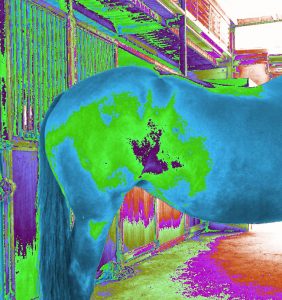

ERIC can detect injuries and sickness with horses.

Pictures show these horses have different body injuries and sickness.

Pictures show these horses have different body injuries and sickness.